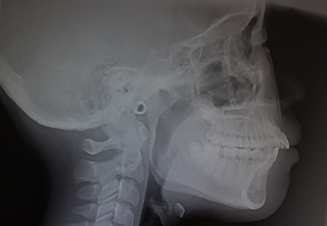

セファロ分析

セファロ分析は、頭部全体を撮影するレントゲンを使用し、矯正治療に不可欠な機器です。治療前の状態から経過を追いながら撮影を行うことで、矯正治療後の変化を確認することができます。撮影を通じて、上下の顎の大きさや形、ずれ、歯の傾斜角度や口元のバランスを把握し、そこから最適な治療計画を立てます。